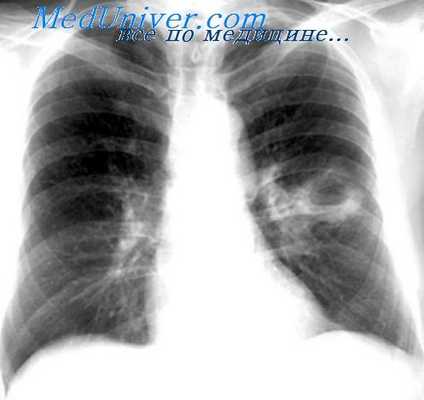

Пульмонэктомии при кавернах легкого. Эффективность комбинированной кавернотомии

Общими показаниями для открытого лечения каверн у всех больных туберкулезом легких являлось наличие больших и гигантских каверн, не поддающихся антибактериальной терапии, которым по тем или иным объективным признакам не показана более «радикальная» операция — резекция пораженного отдела легкого. У всех больных подлежащая вскрытию каверна являлась, по нашему мнению, основным источником интоксикации и основной причиной прогрессирования туберкулезного процесса. Эти общие показания являлись основными для разработки вариантов комбинированной кавернотомии согласно индивидуальным особенностям каждого больного и патологическим изменениям в легких.

Расширение показаний к пульмонэктомии, в том числе и при деструкции в оставшемся легком, выдвигает перед хирургами новую проблему— оказание действенной помощи больным с большими и гигантскими кавернами в единственном легком. Возможности антибактериальной терапии у этой группы больных крайне ограничены, торакопластика не показана из-за низких функциональных резервов легочно-сердечной системы, резекция легкого—вследствии необходимости удаления большей части функционирующей легочной паренхимы. Мышечная пластика вскрытой и оздоровленной каверны, несмотря на абациллярность, не всегда приводит к положительным результатам из-за выраженных дистрофических изменений легочной ткани.

Ближайшая эффективность модификаций кавернотомии составляет, по нашим данным, 80,4% случаев. В сроки наблюдения от года до 17 лет полный клинический эффект сохраняется у 75,6% случаев, основными причинами летальных исходов являются прогрессирование специфического процесса, нарастающая легочно-сердечная недостаточность.

Отдаленные результаты различных вариантов кавернотомии (554 больных) изучены в течение от 2 до 25 лет. Полный клинический эффект сохраняется у 463 человек (83,5%), т. е. клинико-рентгенолотические исследования показали при полном отсутствии признаков туберкулезной (интоксикации, закрытие каверн стойкой абациллярности. Бронхоторакальные свищи с остаточными санированными полостями имелись у 6,1% больных и с бацилловыделением — у 5%. Отдаленная летальность среди наблюдаемых нами больных составила 5,2% при общей летальности — 9%.